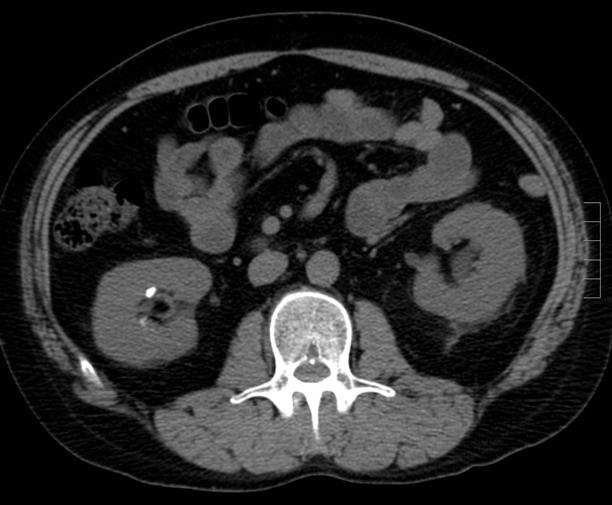

含鈣腎結石的形成,主要是尿液中促進結石形成的物質濃度過高,或抑制結石形成的物質濃度過低。

-A:正確。①尿中鈣離子濃度增加、②尿中尿酸濃度上升、③尿中草酸鹽濃度上升,這三者都是形成含鈣腎結石的常見原因。